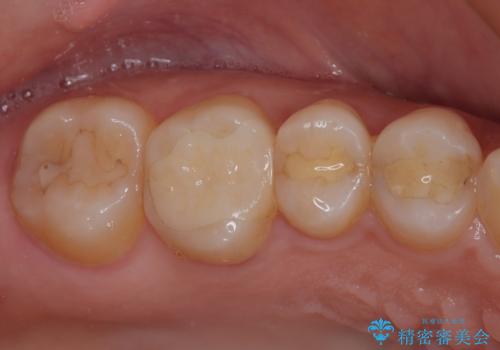

インプラント治療をきっかけに、銀歯を全てセラミックに替えていきました。

人の目を気にせずに、大きく口を開けて笑えるようになりました。